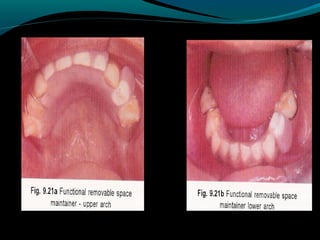

REMOVABLE

APPLIANCE

The appliance is typically used when more than

one tooth has been lost in a quadrant.

It is often the only alternative because there

are no suitable abutment teeth and bacause the

cantilever design of the distal shoe or the band

and loop is too weak to withstand occlusal forces

over a two-tooth span.

Not only can the partial denture replace more

than one tooth, it also can replace occlusal

function.

Two drawbacks of the appliance are retention

and compliance.

REMOVABLE APPLIANCE The appliance istypically used when more than one tooth has been lost in a quadrant. It is often the only alternative because there are no suitable abutment teeth and bacause the cantilever design of the distal shoe or the band and loop is too weak to withstand occlusal forces over a two-tooth span. Not only can the partial denture replace more than one tooth, it also can replace occlusal function. Two drawbacks of the appliance are retention and compliance.

• 29.